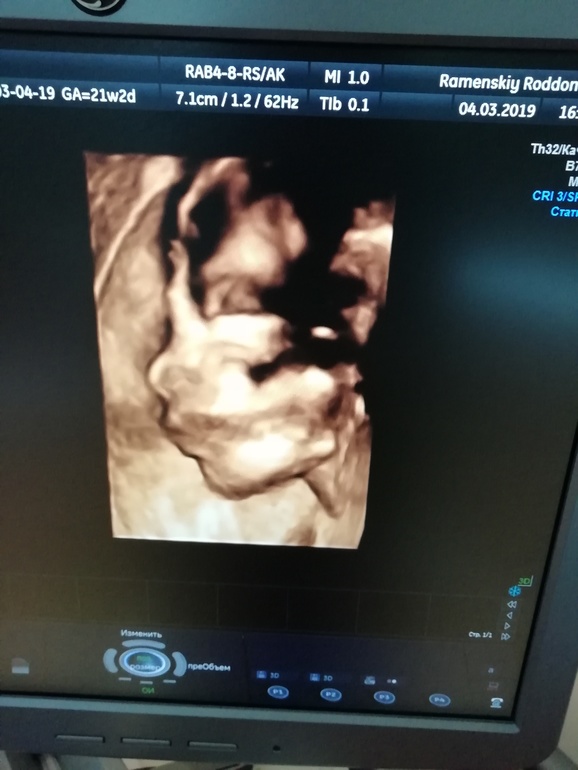

УЗИ, КТГ, доплерСходили мы на 2е узи в жк. Всё хорошо, не считая очереди на 2 часа😣 Малыш развивается в соответствии со сроком, вес 435+-65 гр. Пока сидит попой вниз. Посмеялись с врачом, она говорит - перевернётся, я уже как-то не особо в это верю - все мои мальчики родились в тазовом. Видимо, для нас это уже норма=)). Ну и вот он, мой мальчик.